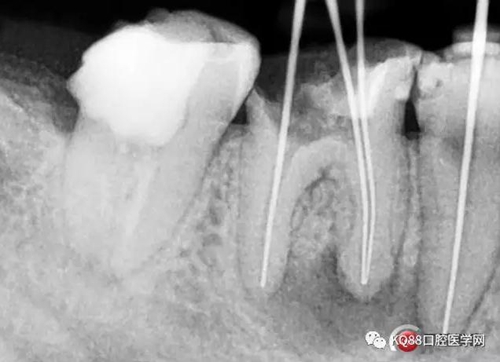

處理與結(jié)果:45局麻去髓,在確定工作長度時拍X線片顯示:46近中根尖周稀疏影,且邊緣呈淡薄云霧狀。

例2 45根管測量時X線片所見